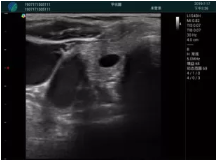

腺體內(nèi)部清晰顯示一低回聲塊影,形態(tài)不規(guī)則,邊界模糊,邊緣呈毛刺狀,內(nèi)部見砂礫樣鈣化

M20引導(dǎo)下穿刺活檢術(shù)